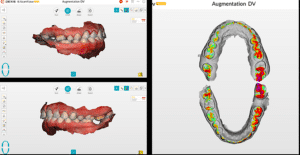

Les photographies et l’empreinte numériques sont envoyées au laboratoire (laboratoire LM2M, Paris 8e). Nous indiquons sur la fiche d’augmenter la DVO pour rétablir l’esthétique du sourire et de créer un wax-up virtuel des deux blocs incisivo-canins. Le laboratoire envoie un fichier 3D sur Exocad avec le wax-up virtuel (Fig.3a, b, c). Cette étape est très importante et permet au praticien de décider du plan de traitement.

Fig.3a, b, c : Le laboratoire envoie un fichier 3D sur Exocad avec le wax-up virtuel.

Fig.3b.

Fig.3c.